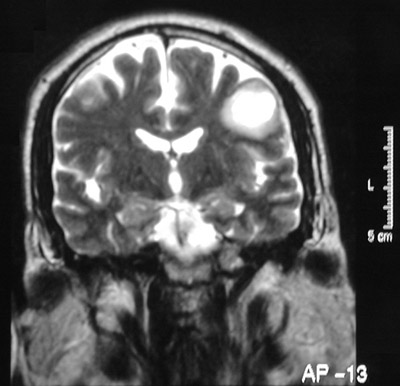

In the T2 weighted scans of the cerebrum above and the cerebellum below both demonstrate enhancing plaques of demyelination while the patient was symptomatic and having an exacerbation of his multiple sclerosis.